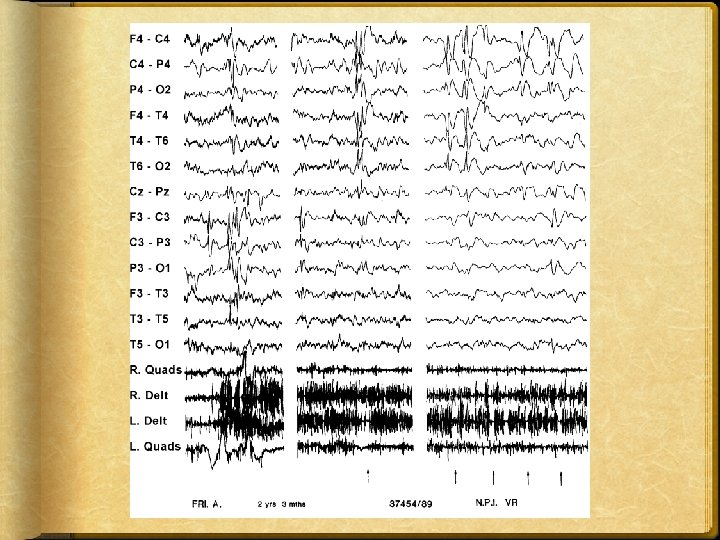

EPILESSIA nell’età EVOLUTIVA ITER DIAGNOSTICO: GLI STRUMENTI ELETTROENCEFALOGRAMMA EEG basale EEG in siesta Poligrafia EEG Holter Video EEG

F. A. 5 anni Bambino con epilessia parziale motoria cripto genetica che da alcuni mesi manifesta tremori distali, perde gli oggetti dalle mani ed inizia a camminare “male”. EEG in veglia standard